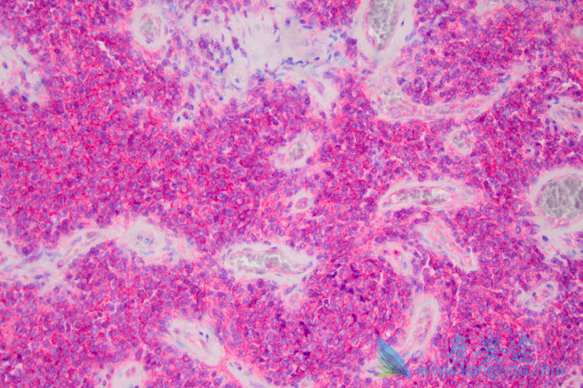

舒尼替尼胶囊(舒尼替尼)能治疗胰腺神经内分泌瘤吗?治疗效果怎么样?在一项随机、对照III期临床试验中,服用舒尼替尼的进展期胰腺神经内分泌瘤患者的无进展生存期间从5.5个月延长治11.4个月。这项研究由法国Eric Raymond博士及同事完成,试验一共入组了171例患者,并将其随机分成口服37.5 mg/日的舒尼替尼治疗组和安慰剂对照组。

由于在已随机入组的154例患者中,安慰剂组大量患者发生死亡和严重不良事件,该研究随即中止。共计44例舒尼替尼组患者和59例安慰剂组患者被纳入本研究分析中。舒尼替尼治疗的中位时间为4.6个月,安慰剂为3.7个月。接受舒尼替尼胶囊治疗超过1年的患者有19例 (22%),安慰剂组为4例(5%)。结果显示,舒尼替尼组的疾病进展风险比为0.42(P<0 .001),舒尼替尼组和安慰剂组的6个月无进展生存率分别为71.3%和43.2%,患者死亡人数分别为9例(10%)和21例(25%),舒尼替尼死亡风险比为0.41 (P=0.02)。

舒尼替尼组8例患者证实有肿瘤应答(2例为完全应答,6例为部分应答),客观应答率为9.3%。安慰剂组未见客观应答。此外,旨在确定可能对疗效产生影响的患者及肿瘤特征的探索性分析表明,所有舒尼替尼胶囊治疗亚组的进展或死亡风险比均优于安慰剂组。舒尼替尼组多数不良事件为1或2级,其中各种常见不良事件(腹泻、恶心、乏力、呕吐以及疲乏)的发生率均超过30%。